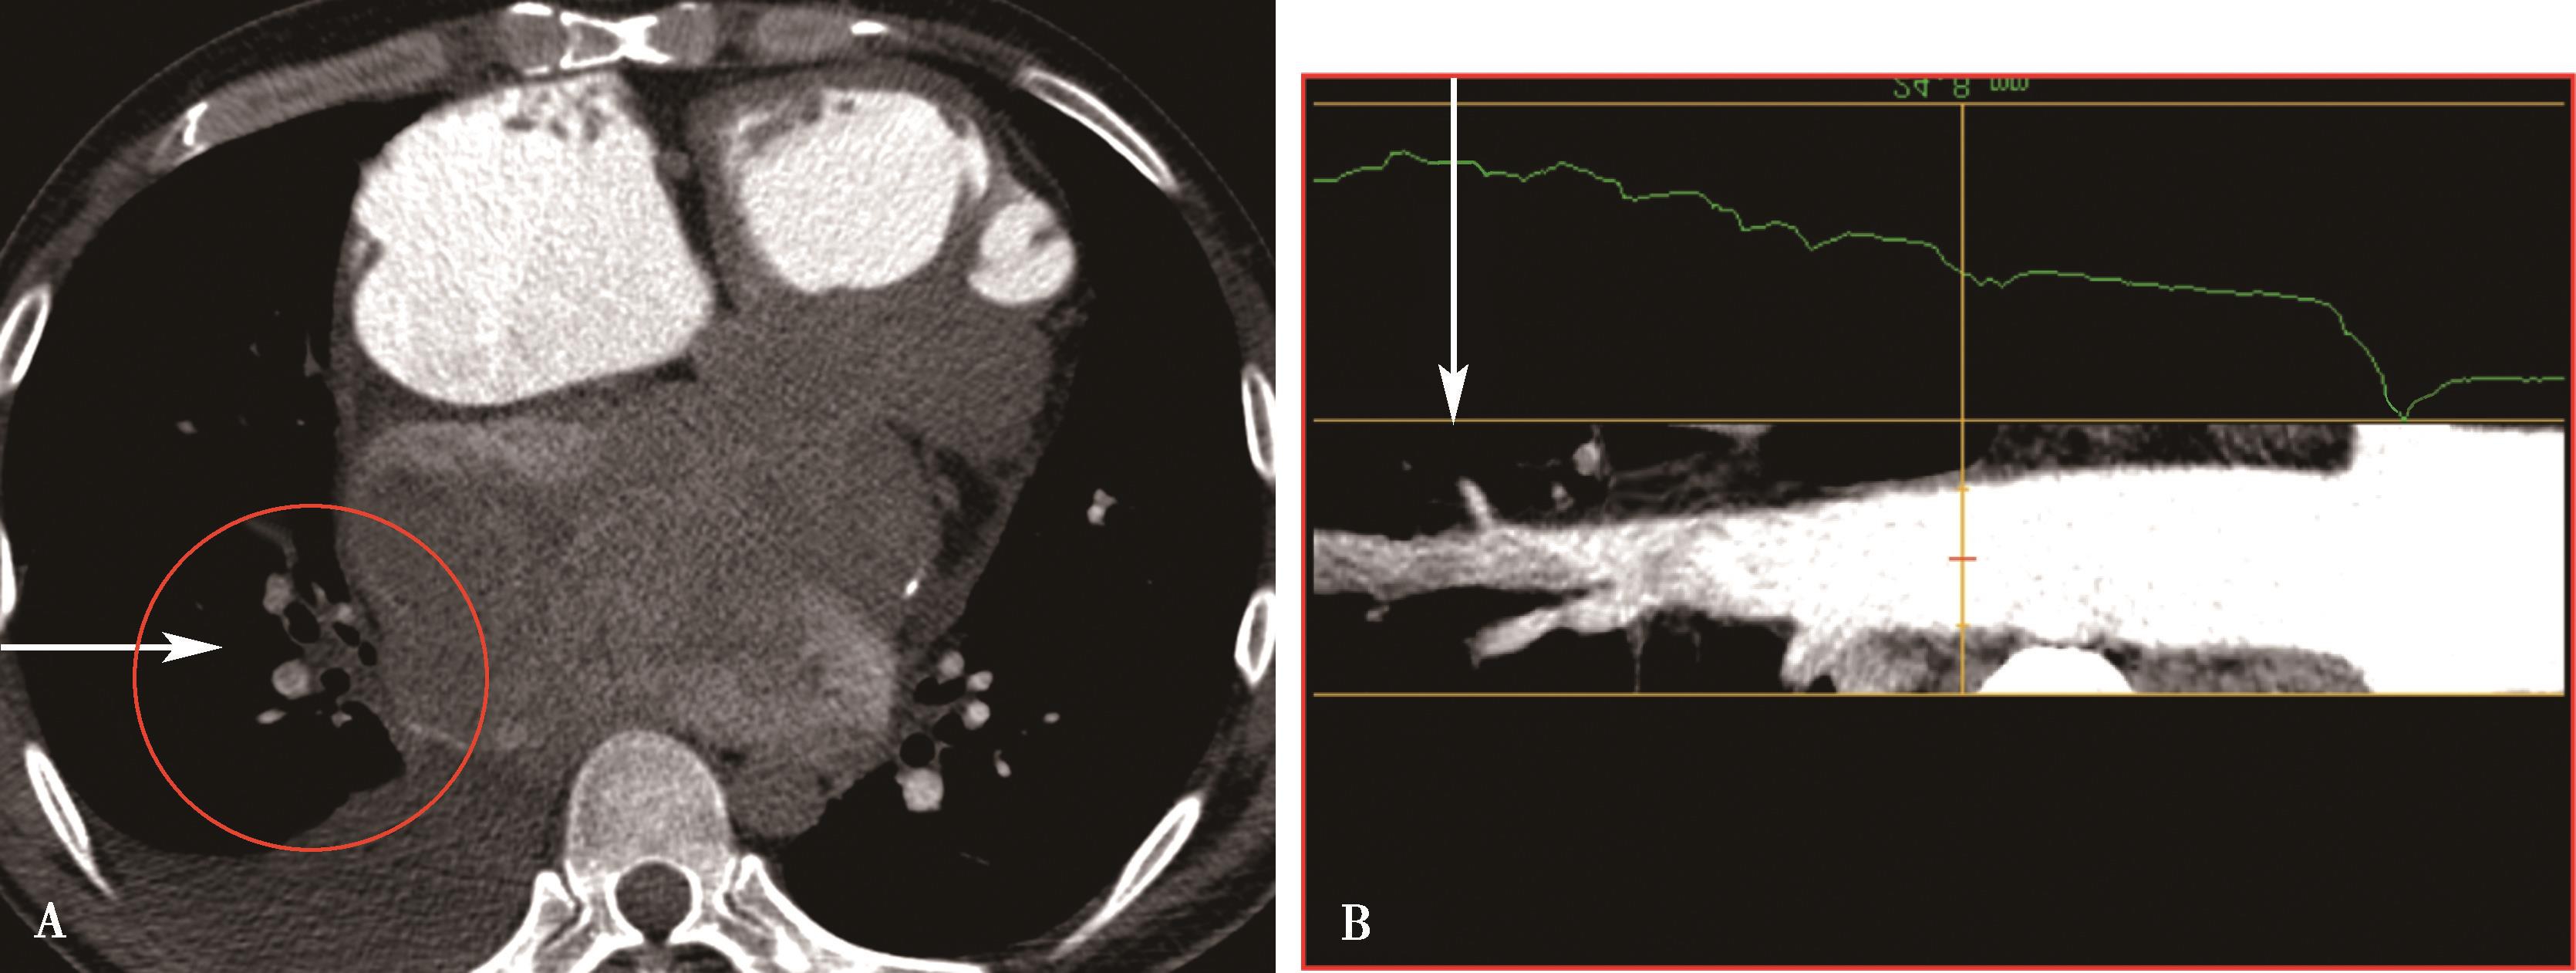

1)主肺动脉干或/和左右肺动脉干梭形瘤样扩张,腔内不同程度附壁血栓(图8-5-4)。

横断图像。A~C.主肺动脉、瘤样扩张,左右肺动脉瘤样扩张,不规则附壁血栓(↑);D~F.三维重建主肺动脉及左右肺动脉瘤样扩张,红色为附壁血栓(↑),波及肺叶分支;CT诊断:肺动脉瘤累及主肺动脉、左右肺动脉及叶分支,附壁血栓形成,病变性质考虑为白塞病